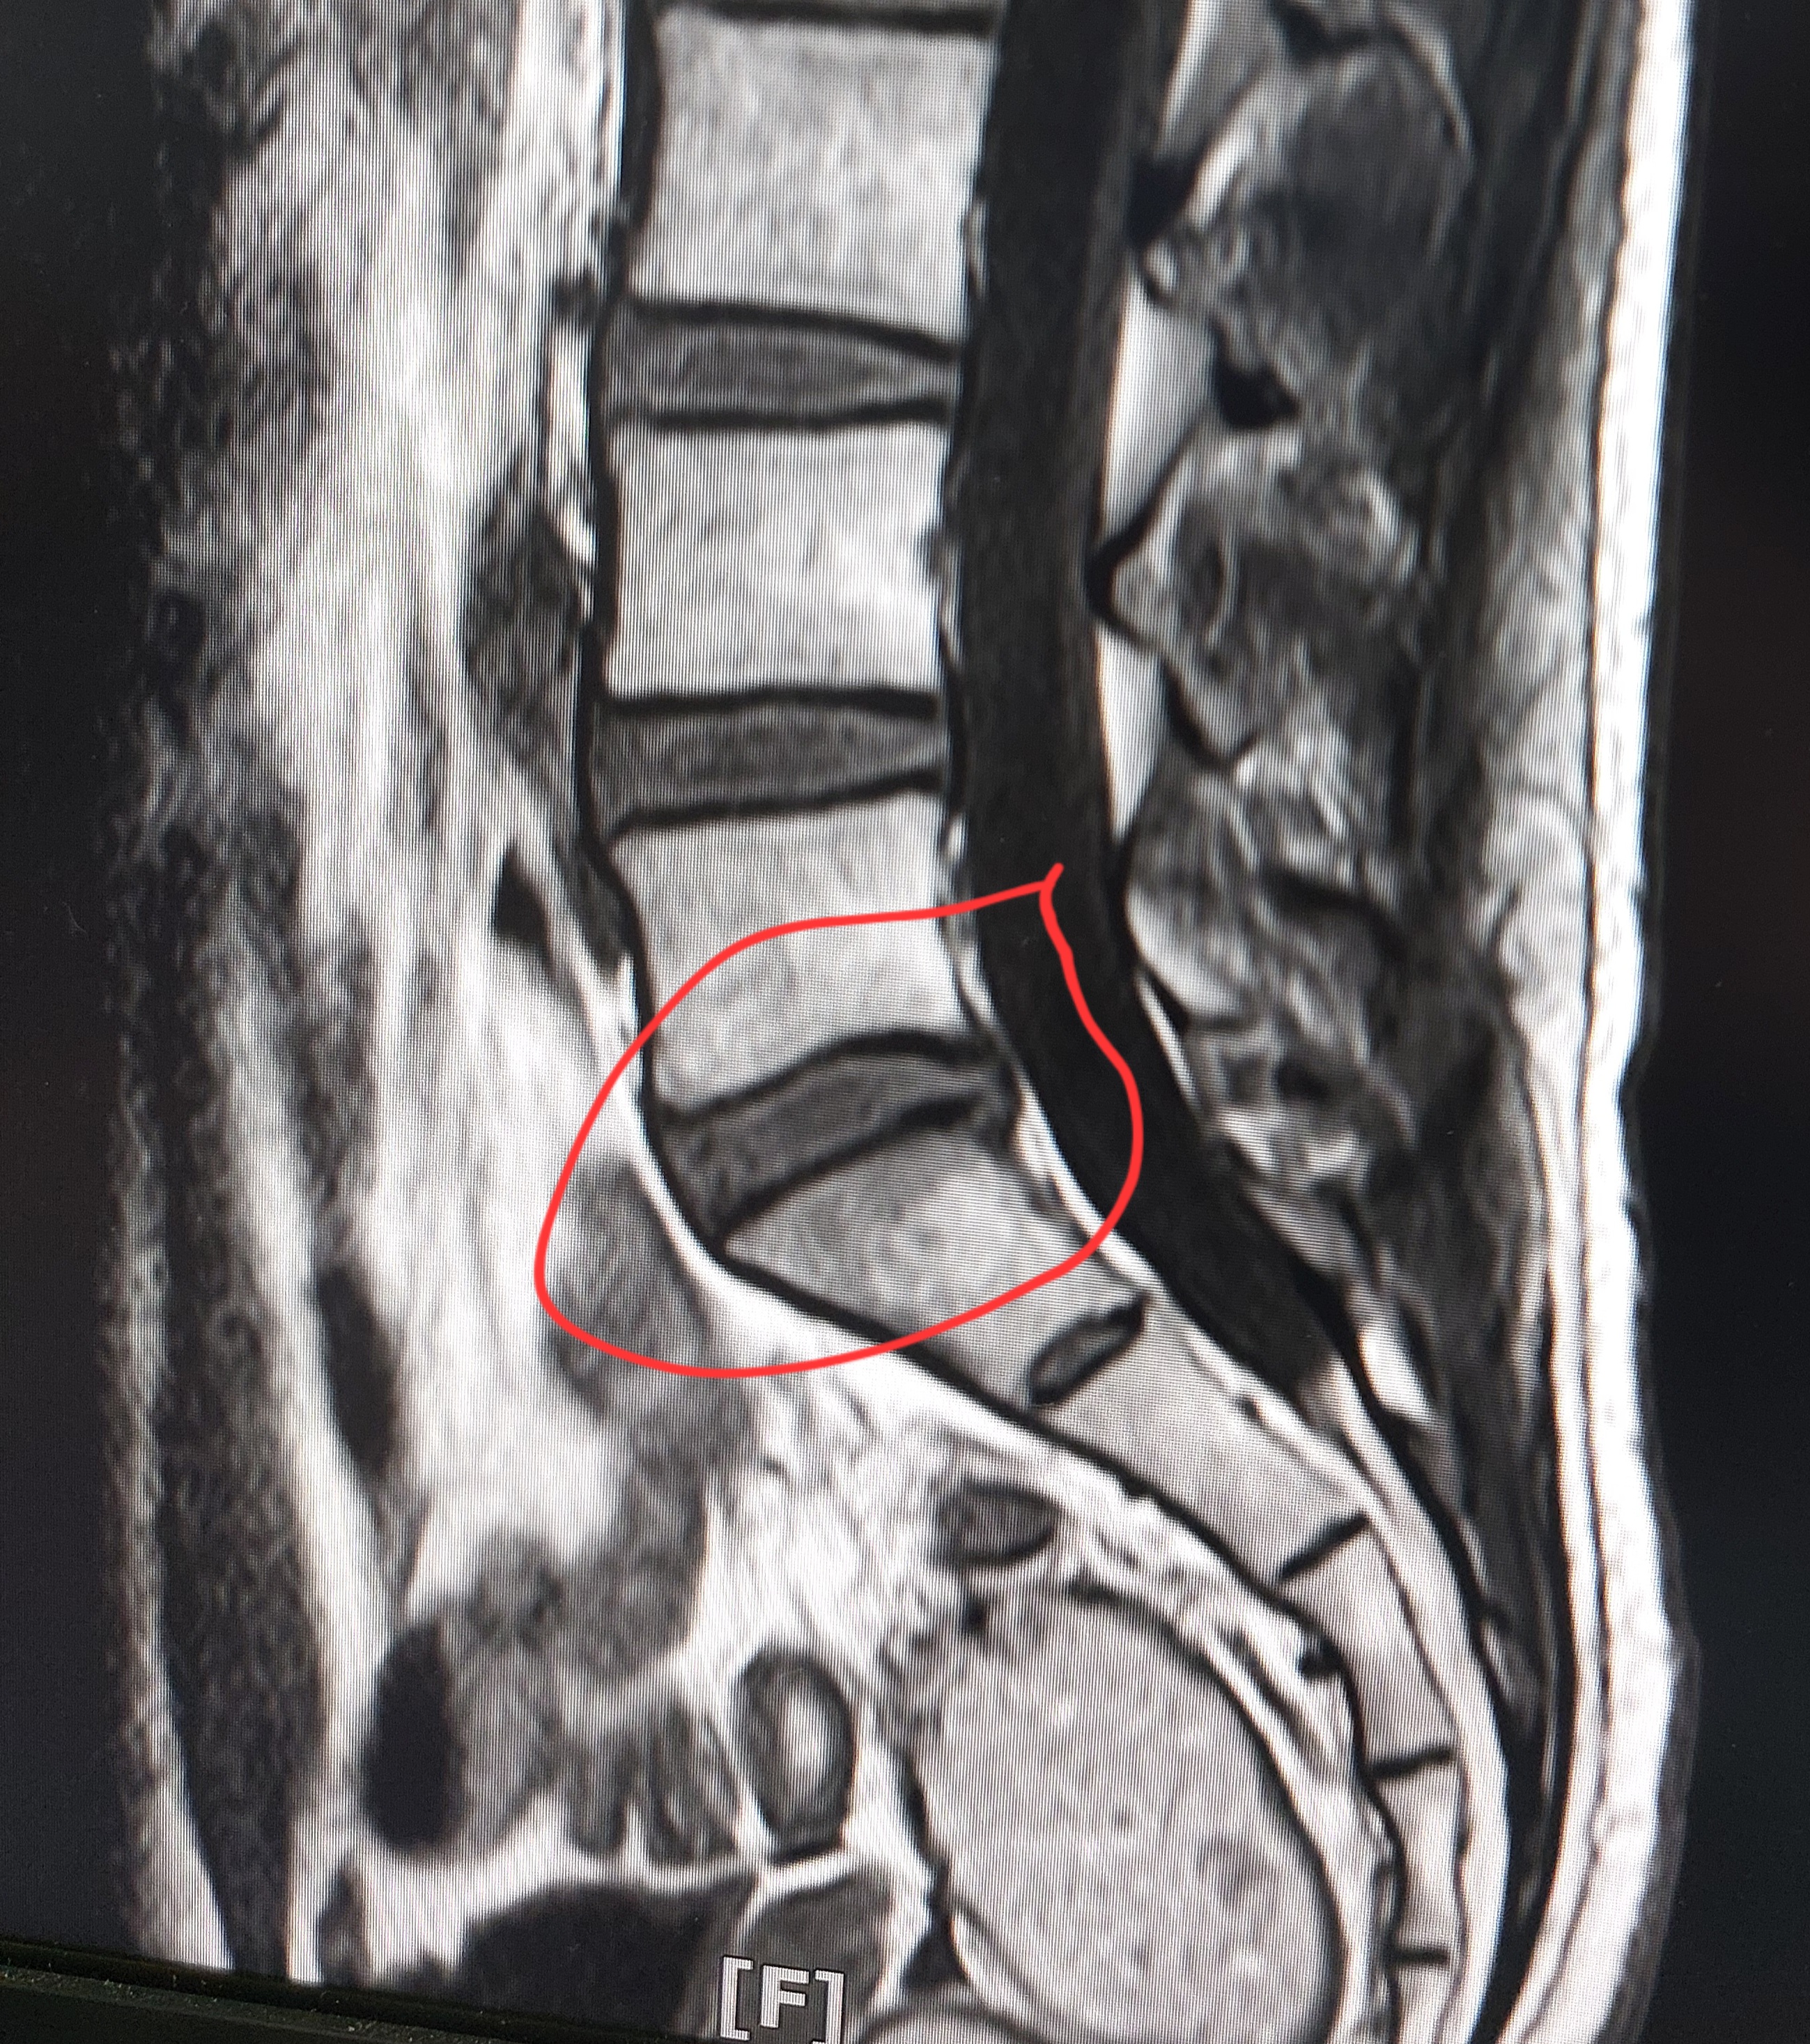

멸개월전부터 요추가 뻣뻣하고 시큰거리다가 최근에 좀 나아지긴 해도 만성적이라서 오늘 mri 찍고 허리디스크 진단받았습니다

(요추 맨 밑 천추 위 디스크)

Mri 찍은 병원은 고주파 시술같은거 하라고 하고 다른병원은 이정도면 잘 쉬면 완치된다고 하는데

1. 이정도면 정상수준이라고 하는 분도 있던데 어느정도 수준인가요?

신경이 심하게 눌리고 있지는 않은 것으로 보입니다. 충분히 휴식하여 주시고, 허리에 무리가 많이가는 자세는 당분간은 피해주시는 것이 좋습니다.